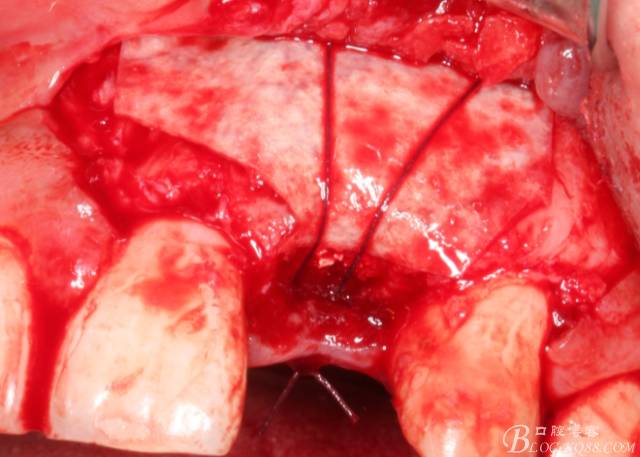

將自體骨與BIO-OOS骨粉混合植到術(shù)區(qū),蓋生物膜。

縫合。